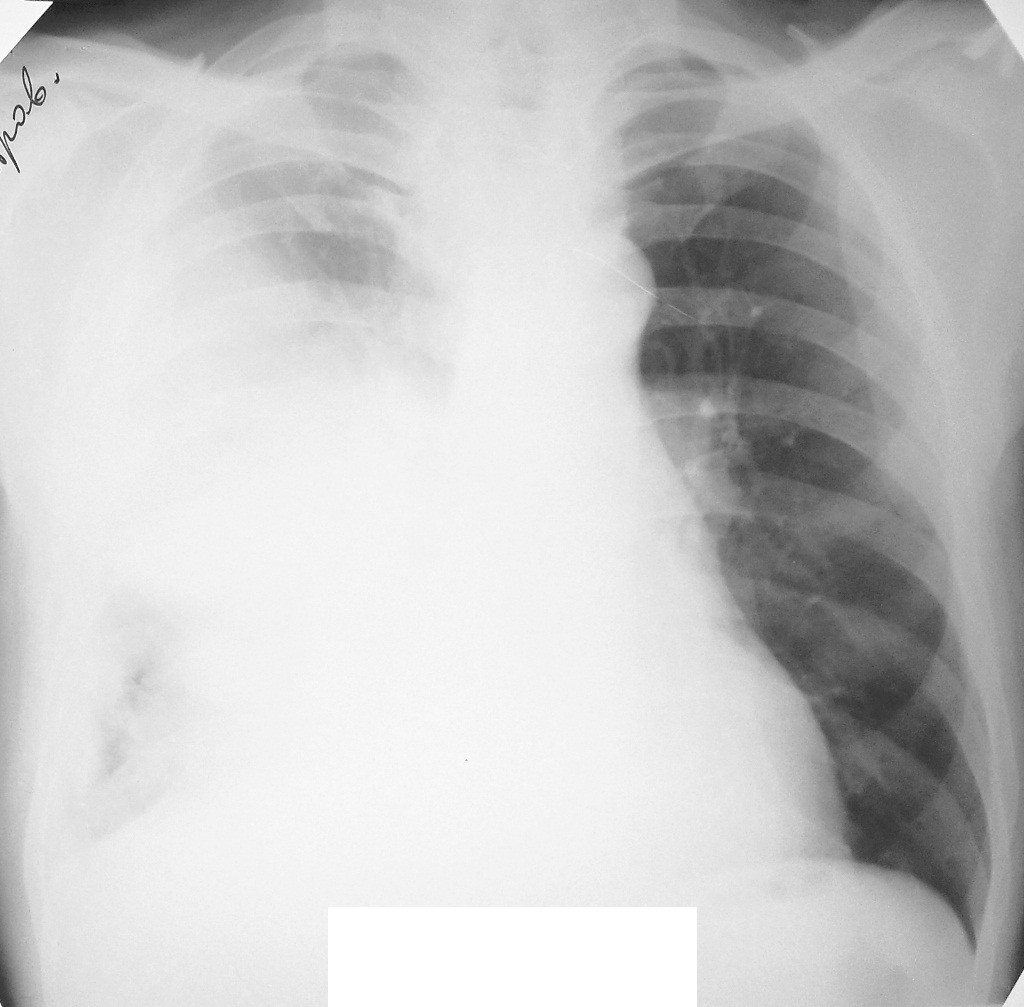

Добавила боковой.

За качество извиняюсь.

Чем подтверждено предположение Nikolas(a) о междолевом выпоте и  ниспровергнуто предположение пульмонолога о центральной опухоли.

При поступлении 6.12. дежурным хирургом назначен обзорный снимок ОГК. После которого назначена консультация терапевта. После ФБС пульмонолог назначил боковой снимок. Утром 7.12. описывала оба снимка. Помимо междолевого выпота, не понравилась какая-то странная пневмония в нижней доле. Решила перестраховаться и взять на КТ. Реконструкции (лежа на спине):

Думаю картина накопления жидкости в междолевых щелях.

Плюс осумкованный паракостальный плеврит по задней поверхности.